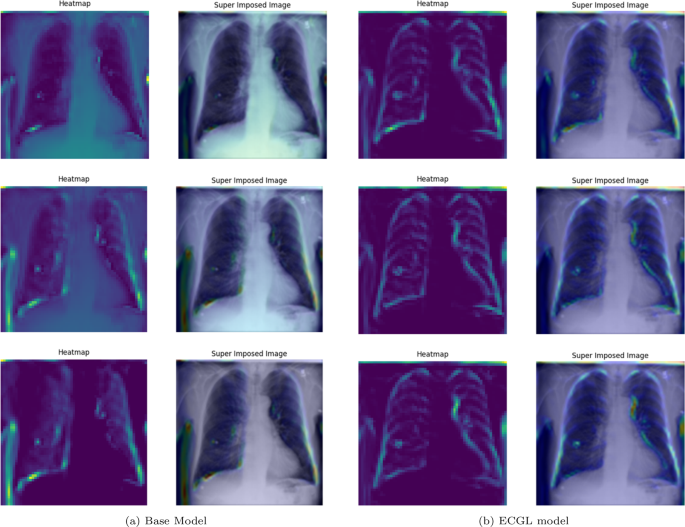

Figures 4 and 5 depict the GradCAM Heatmaps and Superimposed X-ray images of correctly and incorrectly predicted pneumonia instances, respectively. The areas in images that are highlighted in color represent the regions that the model deemed most important for its decision. Moreover, the overlay of the heatmaps on the original X-ray images provides valuable information, allowing us to assess whether the models are focusing on relevant features. The superimposed images refer to the original images combined with the heatmaps, providing a more comprehensible visual representation of the focused regions. The illustrated heatmaps depict three classification outputs corresponding to the labels 0, 1, and 2, arranged from top to bottom, respectively. Label 0 indicates “No Lung Opacity,” which refers to patients without diagnosed pneumonia. The other labels, 1 and 2, on the other hand, signify Lung Opacity and the presence of fuzzy white clouds in the lungs, associated with pneumonia.

GradCAM Heatmaps and superimposed images of the (a) base model and (b) ECGL model for correctly labeled instances. The illustrated heatmaps correspond to GradCAM visualizations for labels 0 (normal), 1 (pneumonia present), and 2 (pneumonia absent, abnormalities exist), arranged from top to bottom, respectively. (a) base Model. (b) ECGL model

Likewise, Figs. 6 and 7 compare the proposed ECGL model and the Base model in terms of explainability by using GradCAM heatmaps. While both models generally seem to be focusing on similar areas (central region) of the chest X-rays, the color intensity in the heatmaps and superimposed images obtained from the ECGL model clearly shows a greater emphasis on certain regions that are related to the respiratory system and pneumonia disease. As it can be seen in Fig. 4(a) and 4(b) (correctly labeled instances), the highlighted regions of the Base model are more blurred, hazy, and spread out across the image, suggesting that the model’s decisions are less interpretable and apparent to the experts. Whereas the proposed ECGL model presents more focused and localized highlighted regions, showing that the model is primarily relying on specific areas of the image, relating to the particular region attacked by the disease, to make its prediction. The ECGL model makes it easier to understand the model’s reasoning and therefore presents more explainability. In addition, the ECGL model produces a more concentrated heatmap, indicating more confidence in prediction.

GradCAM Heatmaps (left column) and Superimposed images (right column) of the (a) Base model and (b) ECGL model for correctly labeled instances. The illustrated heatmaps correspond to GradCAM visualizations for labels 0 (normal), 1 (pneumonia present), and 2 (pneumonia absent, abnormalities exist), arranged from top to bottom, respectively